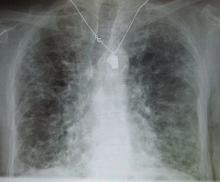

Approach to ILD in Myositis Syndromes

Mehta et al have published a full read review of managing interstitial lung disease (ILD) in patients with inflammatory myopathies, a heterogeneous group of syndromes connected by ILD and and increased morbidity and mortality risk.

They divide myositis-ILD into three main prognostic groups with different treatment approaches: